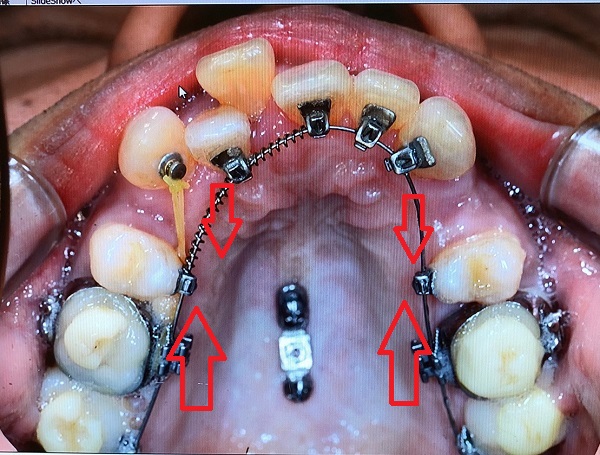

通常、矯正の場合ワイヤーでつながれた歯はお互いを引っ張り合います。

したの画像で言うと、抜歯した4番の穴を境目にして前歯側と奥歯側は引っ張りあうことになります。

前歯も奥歯も動くので抜歯したすき間を前歯の矯正のために有効活用できない可能性が出てきます。

矯正用のインプラントを利用すると・・・

赤○内のインプラントから両側の奥から2番目を結束して固定(※画像では青い直線でつないだイメージにしています)すると、奥歯が前方向に動くことを抑制します。

アンカーインプラントのアンカーとは碇のことです。

インプラントが碇の役目をして動こうとする歯をとどめます。

そして、前歯側が後ろに下げられるスピードが速くなります。

私の場合、抜歯のすき間がふさがるスピードが速くなるのとあわせて、前歯のガタガタもなおり、綺麗なアーチ型ができるスピードが上がります。